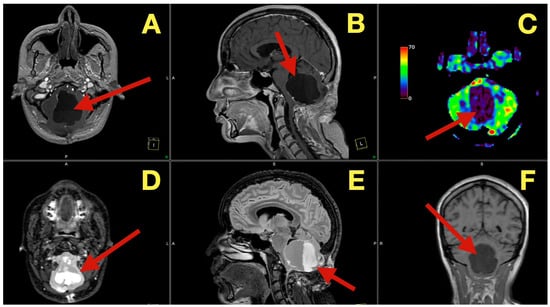

MRI scans five months after surgery (Figure 7), demonstrated that the post-operative cavity contained fluid with no enhancement and normal perfusion of the surrounding parenchyma, with no glial scar on FLAIR and no diffusion restriction on DWI, effectively ruling out remaining keratinous material.

Figure 7. Five-month postoperative MRI. (A): Axial T1-weighted image demonstrating a CSF-filled postoperative cavity with smooth margins and no enhancing tissue (arrow). (B): Sagittal T1 image showing sustained patency of the fourth ventricle and normal vermian convexity (arrow). (C): Axial perfusion map revealing normal parenchymal hemodynamics in the cerebellum surrounding the resection site (arrow). (D): Axial diffusion-weighted image showing absence of restricted diffusion, excluding residual keratinaceous material (arrow). (E): Sagittal FLAIR sequence illustrating clean CSF spaces and absence of gliosis (arrow). (F): Coronal T1 image confirming midline symmetry and complete restitution of cerebellar and brainstem anatomy (arrow).